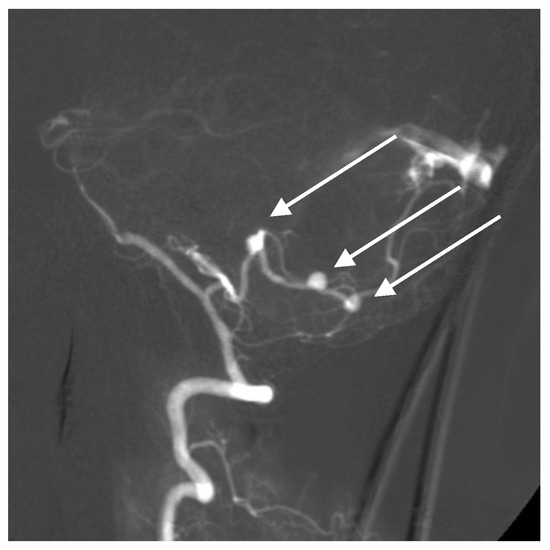

A 52-year-old woman presented with atypical headaches on an acute stage. MRI and subsequent PAG revealed an AVM of the cerebellar convexity with three aneurysms on parent arteries at the SCA and AICA bifurcations (Figure 3). The patient was treated by microsurgical clipping and resection of the AVM. Her postoperative course was uneventful, and follow-ups are undertaken every year.

Figure 3. Multiple superior cerebellar artery (SCA) and AICA aneurysms along with cortical arteriovenous malformation (AVM) of the cerebellum on lateral angiogram highlighted with arrows.